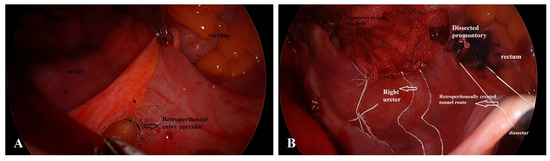

Concomitant Hysterectomy and vNOTES-Assisted Sacrocolpopexy: A Feasible and Safe Scarless Approach for Apical Prolapse Repair

by Ali Deniz Erkmen and Kevser Arkan

Background/Objectives: Durable apical support after hysterectomy is crucial to prevent subsequent vaginal vault prolapse. Abdominal sacrocolpopexy remains the gold standard but carries risks of visceral injury and wound morbidity. The vaginal natural orifice transluminal endoscopic surgery (vNOTES) approach provides a scarless, minimally invasive [...] Read more.

Background/Objectives: Durable apical support after hysterectomy is crucial to prevent subsequent vaginal vault prolapse. Abdominal sacrocolpopexy remains the gold standard but carries risks of visceral injury and wound morbidity. The vaginal natural orifice transluminal endoscopic surgery (vNOTES) approach provides a scarless, minimally invasive alternative, but data on vNOTES-assisted sacrocolpopexy (vNOTES-SC) performed concurrently with hysterectomy remain limited. Methods: A retrospective cohort of 30 women with stage II uterine prolapse underwent concomitant hysterectomy and vNOTES-assisted sacrocolpopexy between January 2023 and January 2024. Anatomical outcomes were evaluated using the Pelvic Organ Prolapse Quantification (POP-Q) system preoperatively and at 12 months postoperatively. The primary endpoint was anatomical success (C ≤ −1 cm); the secondary endpoint used the IUGA criterion (C < −TVL/2). Complications were graded using the Clavien–Dindo classification. Statistical analyses included Wilcoxon signed-rank tests, effect-size estimation, ROC analysis, logistic regression, and Spearman correlation. Results: Mean operative time was 100.2 ± 11.7 min, mean blood loss 155.3 ± 74.8 mL, and mean hospital stay 1.5 ± 0.7 days. Significant improvements were seen in Aa, Ba, C, and Bp points (p < 0.001). Anatomical success (C ≤ −1 cm) was achieved in 73.3% and clinical success in 93.3% of patients. Two patients exhibited anatomical recurrence (6.7%), whereas one patient reported symptomatic recurrence (3.3%). Using the IUGA definition, anatomical success increased to 83.3%. The difference between strict success (C ≤ −1 cm) and IUGA success (C < −TVL/2) reflects definitional sensitivity, particularly in post-hysterectomy vaginal length. All complications were minor (Grade I–II). ROC analysis showed age as a weak predictor (AUC = 0.67). Effect sizes were large for apical and anterior compartments (Cohen’s d = 1.84 for C-point). Conclusions: Concomitant hysterectomy with vNOTES-assisted sacrocolpopexy is a feasible, safe, and effective scarless approach for apical support restoration. The procedure provides significant anatomical correction and rapid recovery with low morbidity. Patients had symptomatic stage II prolapse with risk factors for early failure after native-tissue repair, supporting the selection of sacrocolpopexy for durable apical support. Larger prospective trials are needed to confirm long-term efficacy and functional outcomes. Full article

Show Figures

Figure 1